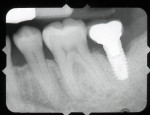

A 64-year-old female patient experienced early loss of attachment due to peri-implantitis as seen in a July 2012 periapical radiograph of an implant placed at the No. 18 site (Figure 1). Fifteen months later examination revealed marked progression of attachment loss and increase in probing depth (Figure 2).